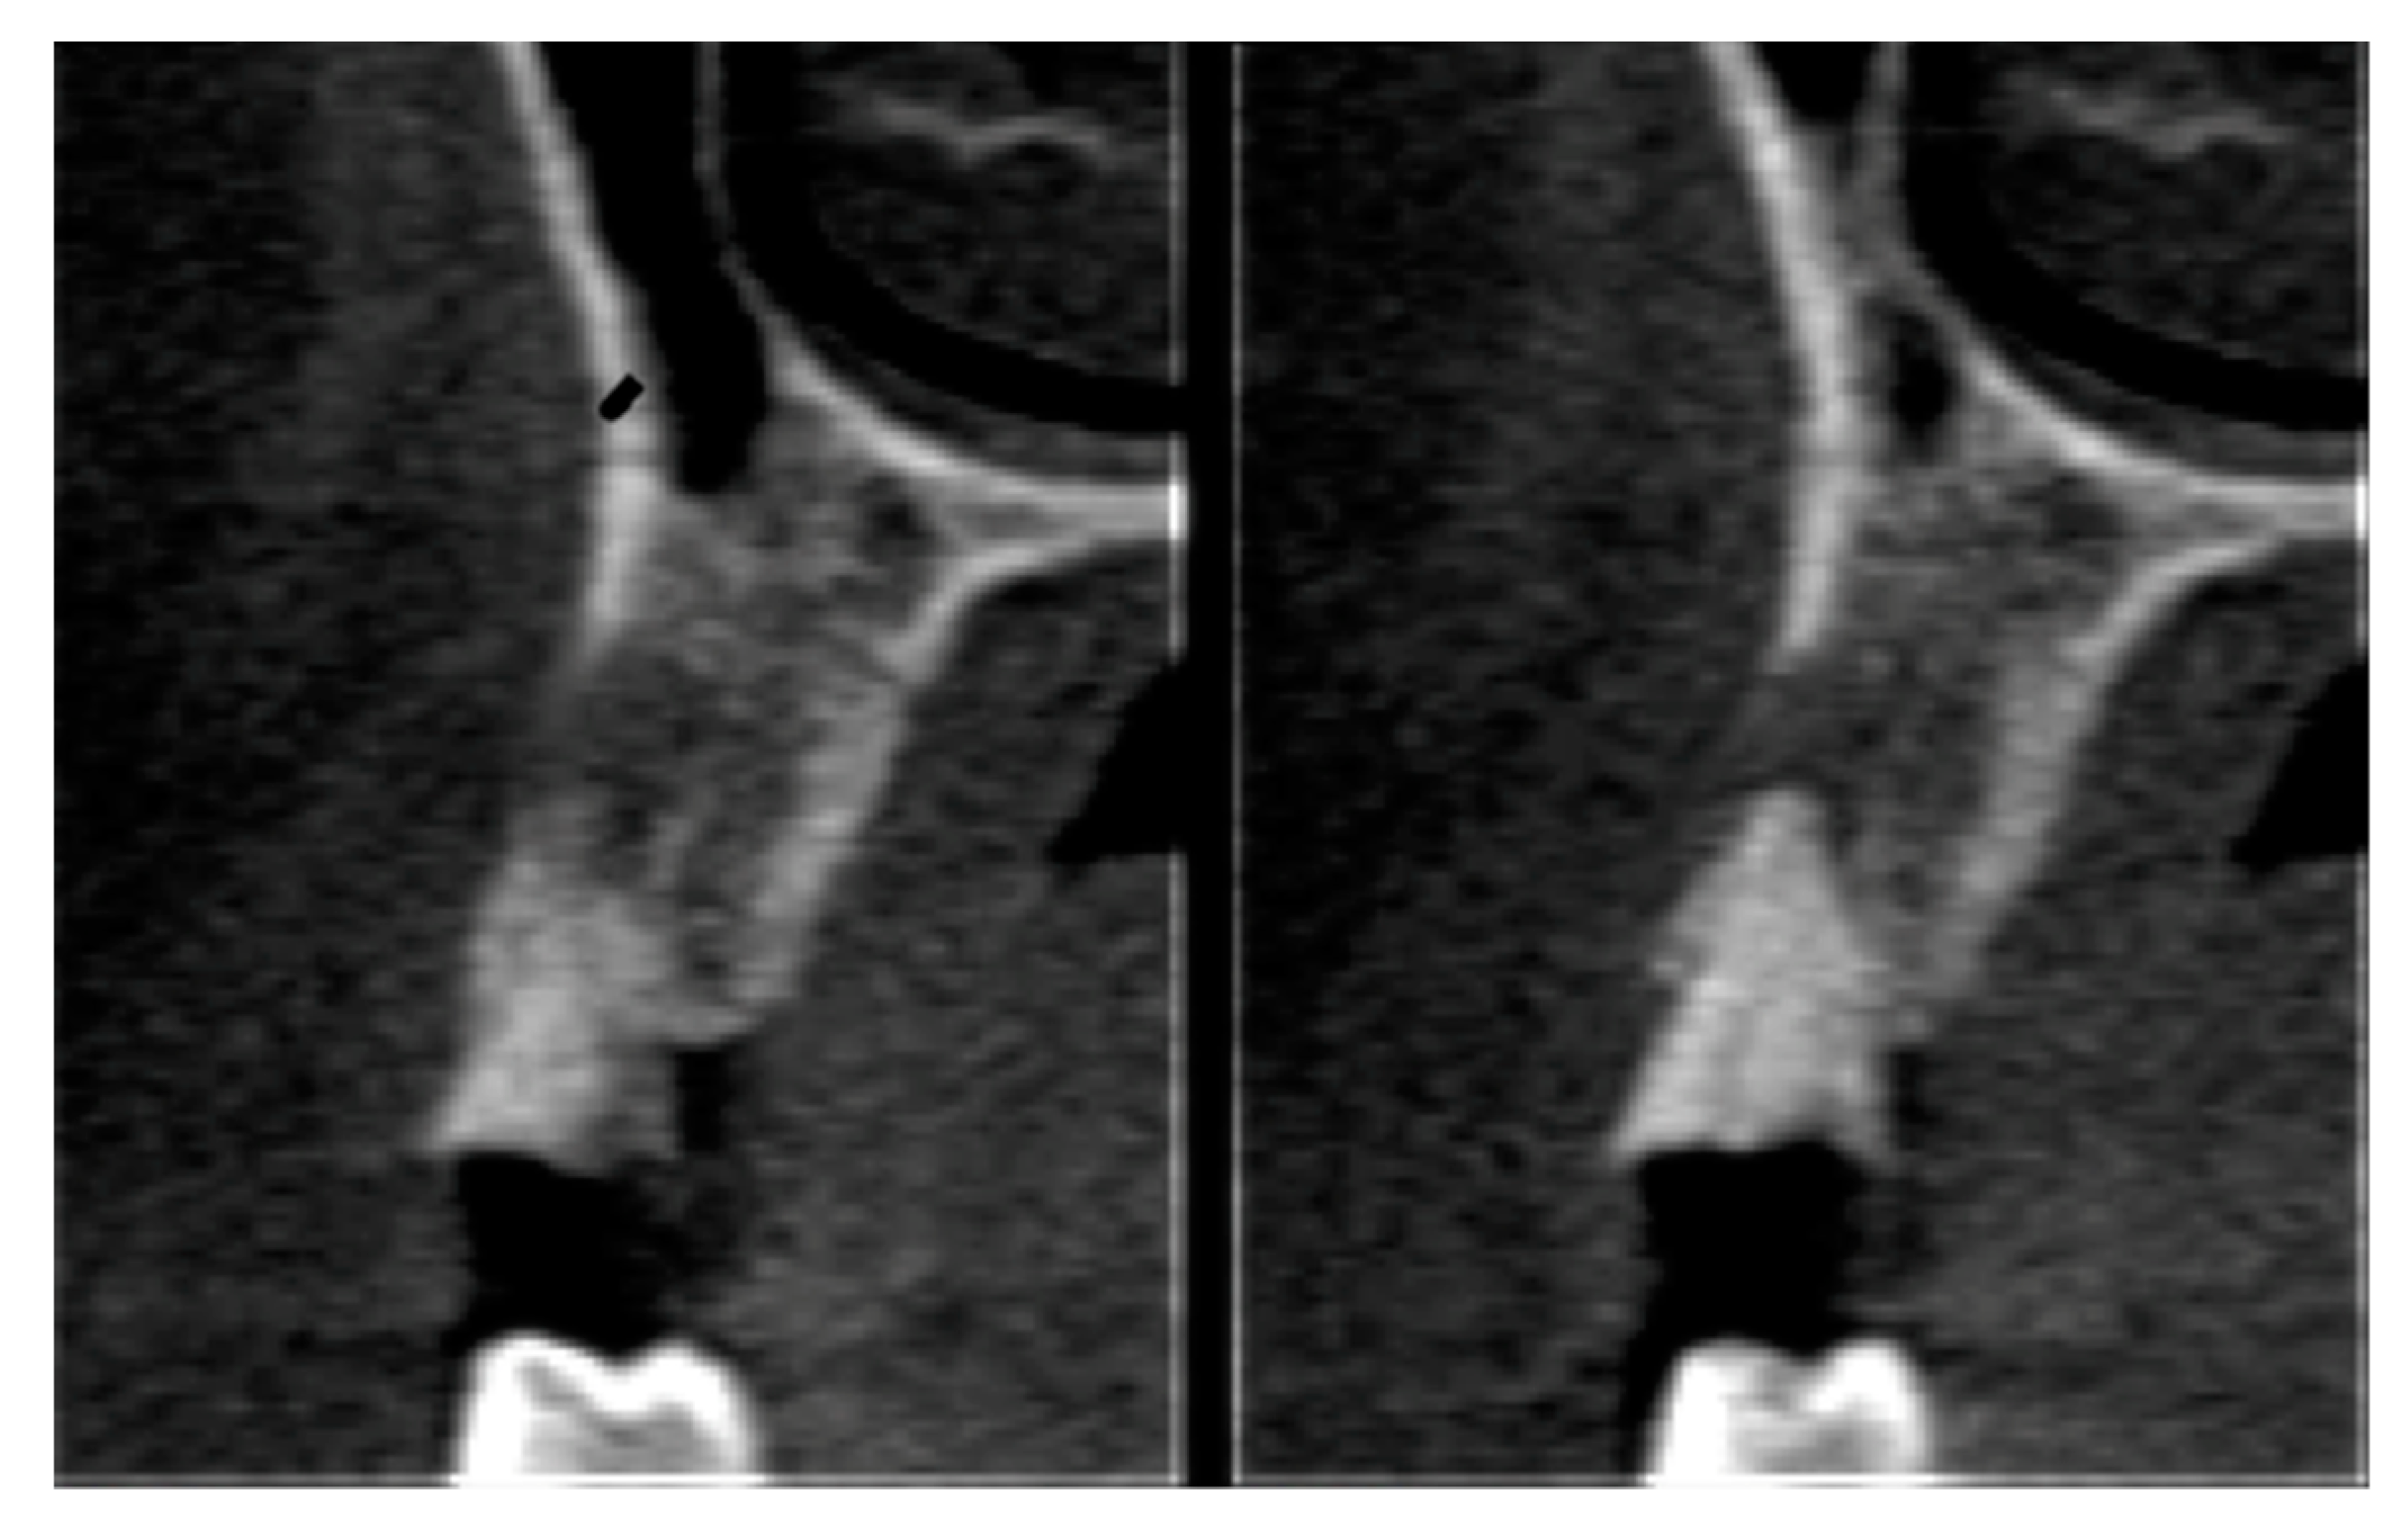

2.6. Tomographic Analysis

| Parameter | Control | Test | P Value | ||

|---|---|---|---|---|---|

| Mean | Standard Deviation | Mean | Standard Deviation | ||

| Buccal plate | 0.46 | 3.04 | 1.11 | 0.91 | 0.417 |

| Socket height | −0.41 | 0.76 | 0.35 | 1.16 | 0.049 |

| Cervical third | −0.89 | 0.71 | −0.11 | 0.73 | 0.008 |

| Medium third | −0.64 | 0.57 | −0.50 | 0.32 | 0.002 |

| Apical third | 0.09 | 0.60 | −0.14 | 0.69 | 0.348 |